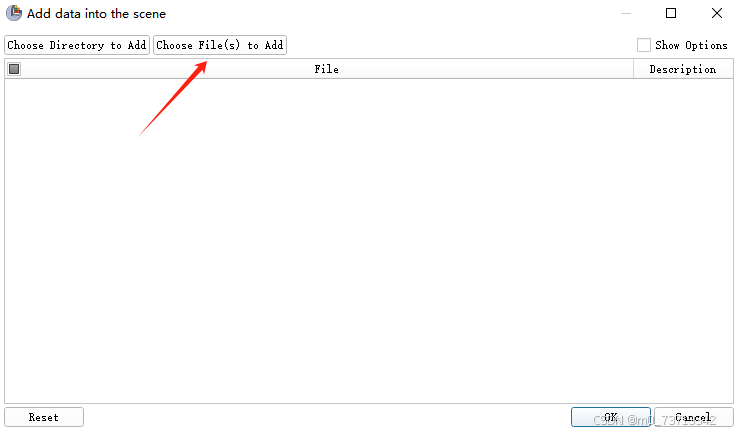

1.将病人数据导入3D Slicer

依次点击如下按钮

选择病人所有dicom图像(全选快捷键CTRL+A)导入得到如下视图